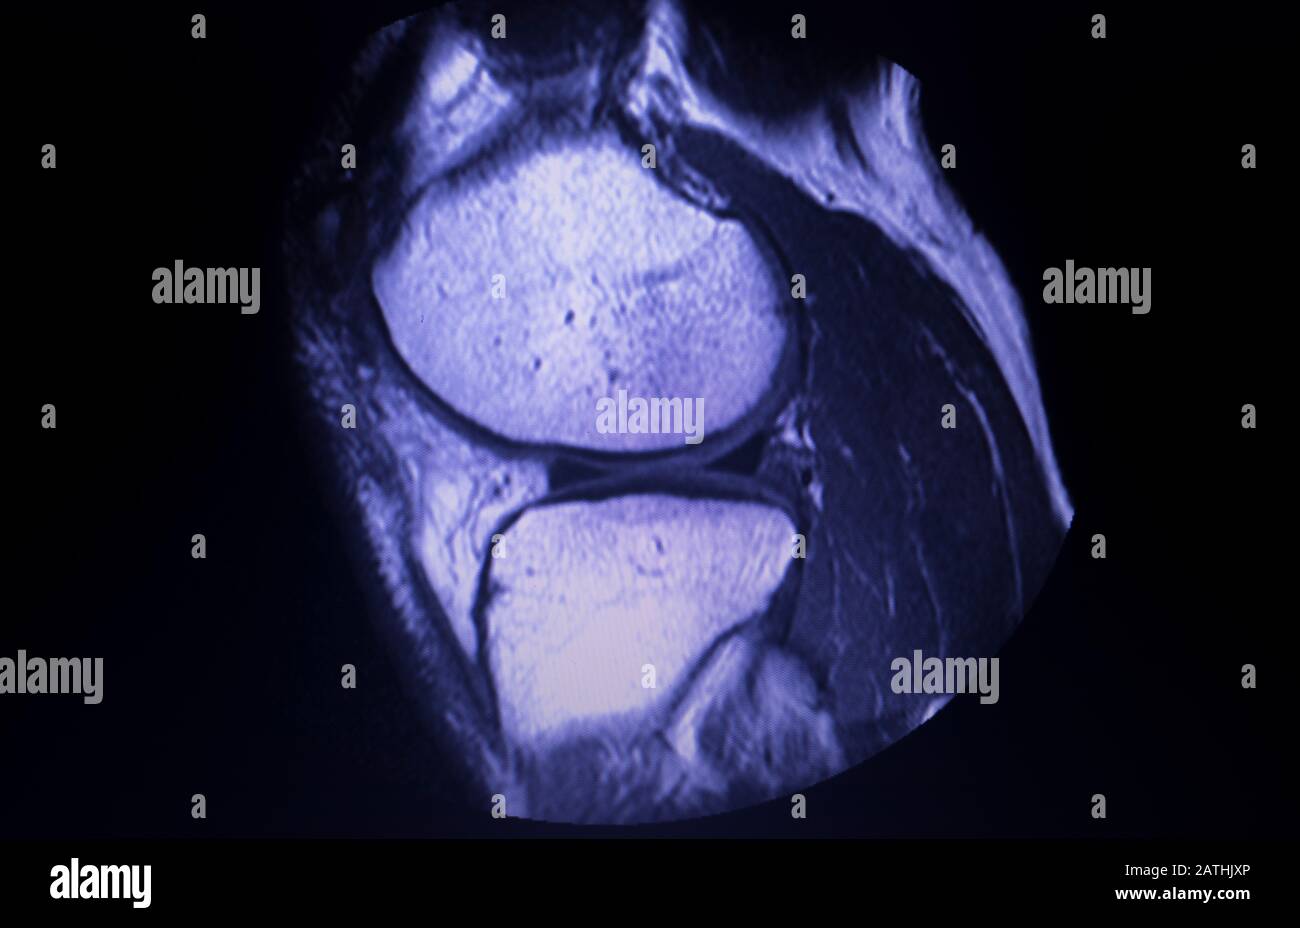

Resonance Imaging Mri Knee Posterior Horn Medial Meniscus Tear Where Is The Posterior Horn Located In medical terms this means that of the two. The posterior horn of the medial meniscus is the most common part of the medial meniscus to be injured. By location, the meniscus can be divided into a (i) posterior horn, (ii) body, and (iii) anterior horn. The most common location for a meniscus tear is in the back of the. Where Is The Posterior Horn Located.

resonance imaging MRI knee posterior horn medial meniscus tear Where Is The Posterior Horn Located This part of the meniscus does not have a. The posterior horn of the medial meniscus is the most common part of the medial meniscus to be injured. The posterior horn of the lateral meniscus includes the main body of the lateral meniscus, posterior to the popliteus tendon, and its root attachment on the posterior aspect of the tibia. In. Where Is The Posterior Horn Located.